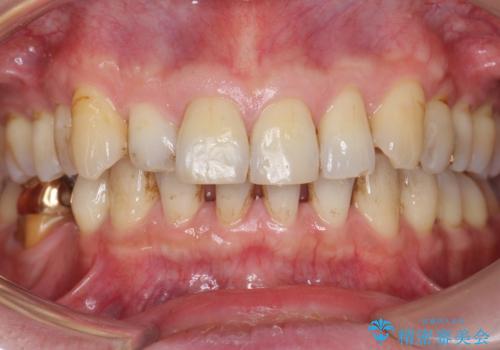

ゴールド(PGA)クラウンの自然な咬み心地とブリッジの審美的な仕上がりに喜んで頂けました。

モチベーションが上がり、ホワイトニングもご希望され補綴前に行いました。

右下の小臼歯(右下5)を他院で抜歯されたことを後悔されており、「はやくこの病院に来ていれば良かったなあ」とおっしゃって下さいました。

右下7:ゴールド(PGA)クラウン

右下⑥5④ブリッジ:オールセラミッククラウン スタンダード